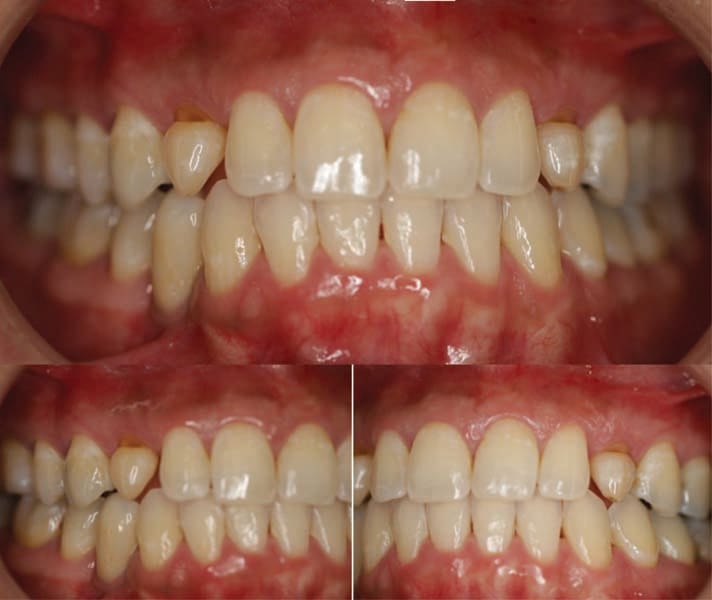

The patient returned and the provisional crowns were removed and cement cleaned from the abutments. The final crowns (lab processed from Jason J. Kim Dental Aesthetics) were tried in and margins checked with an instrument. The occlusion was checked and verified light occlusion was present on occlusion and there were no contacts in excursive movements. The crowns were cemented to the abutments with FujiCEM. Following setting of the cement marginal cement was cleaned with an instrument and a radiograph taken to confirm crown fit to the abutments and no residual cement subgingivally (Figure 20). The patient was given a mirror to evaluate the esthetics of her new smile and indicated she was happy with results, commenting it looked natural (Figure 21 through Figure 24). She was placed on regular 6-month prophy recall.